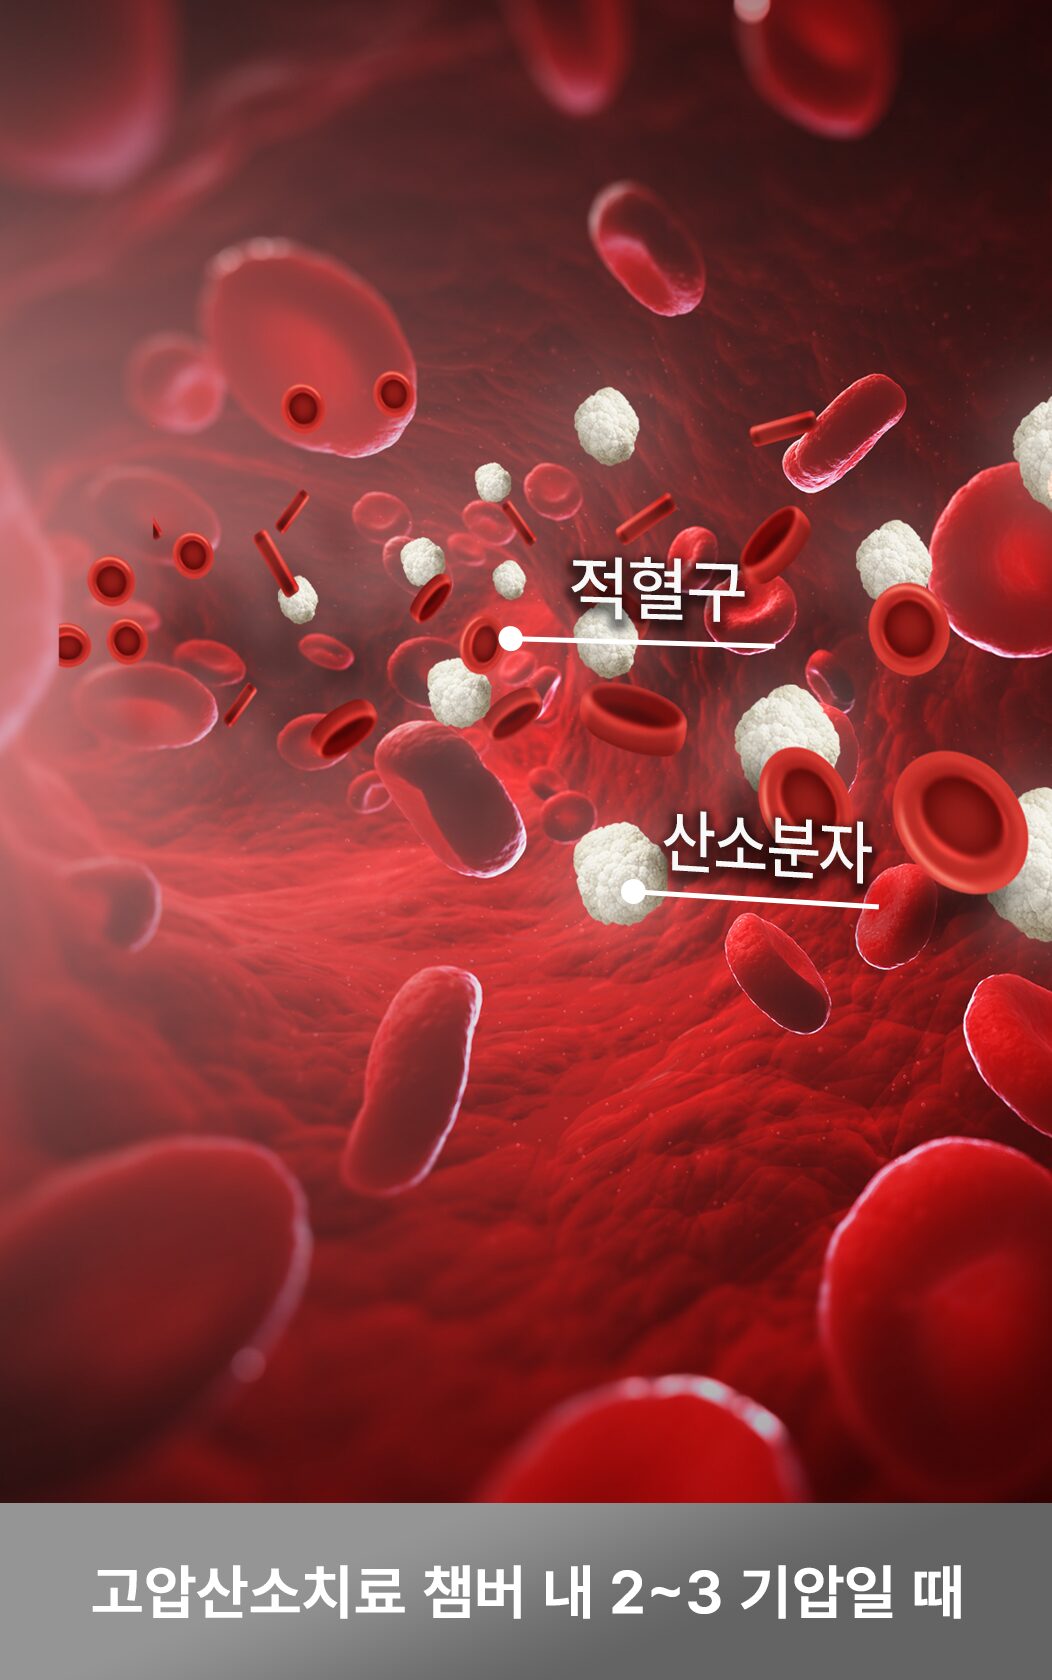

새로운 혈관도 생성이 되나요?

기압을 높이면 적혈구와 결합하지 않아도 산소 분자 그대로 혈액 속으로 녹아들어 모세혈관과 세포까지 활성화되어 새로운 혈관들이 생성될 수 있는 환경을 조성합니다